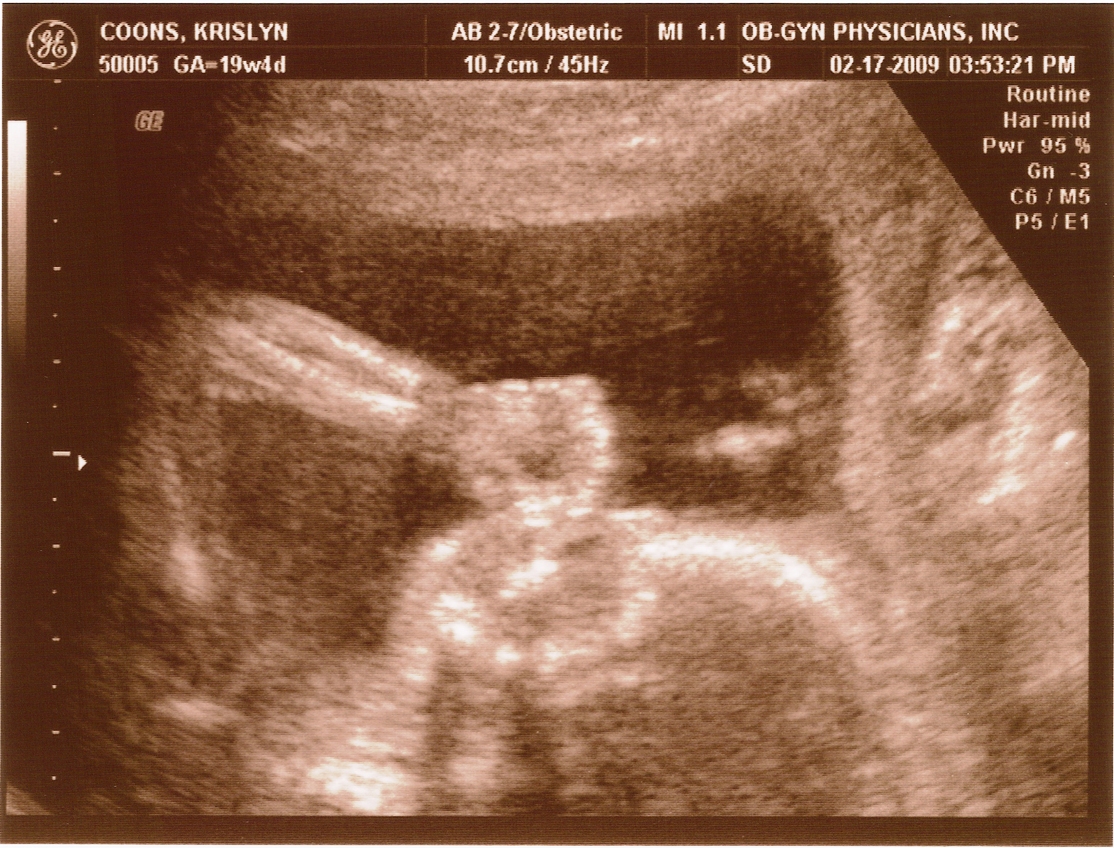

Ultrasound Pictures

20 weeks -

20 weeks